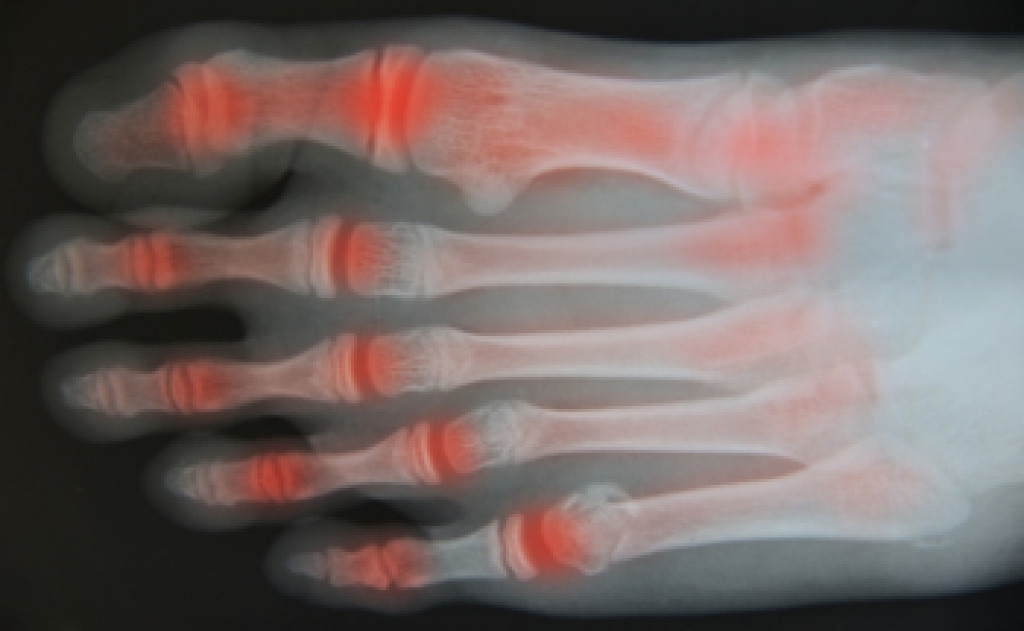

Diabetic neuropathy most often affects the peripheral regions or extremities, including the feet, which tend to bear the greatest brunt of diabetic nerve damage. Prolonged periods of uncontrolled high blood sugar can trigger a number of problematic conditions that can afflict your feet, collectively termed the diabetic foot. This encompasses a range of issues, ranging from neuropathy related numbness and tingling to more severe complications such as ulcers and infections. Proper diabetes management, a healthy lifestyle, and regular check ups with a podiatrist are essential for preventing or managing this condition, particularly when it affects the feet and lower limbs. Early intervention and a proactive approach to diabetic neuropathy can make a significant difference in preserving your overall well being. If you develop a cut or sore on your foot that does not show signs of healing over time or becomes infected, it is essential to consult a podiatrist as soon as possible. Burning sensations, tingling, weakness, or pain in your feet are often early signs of neuropathy, and should be addressed promptly. For help with this condition, it is suggested that you make an appointment with a podiatrist, who is medically trained to treat diabetic neuropathy.

Diabetes affects millions of people every year. The condition can damage blood vessels in many parts of the body, especially the feet. Because of this, taking care of your feet is essential if you have diabetes, and having a podiatrist help monitor your foot health is highly recommended.